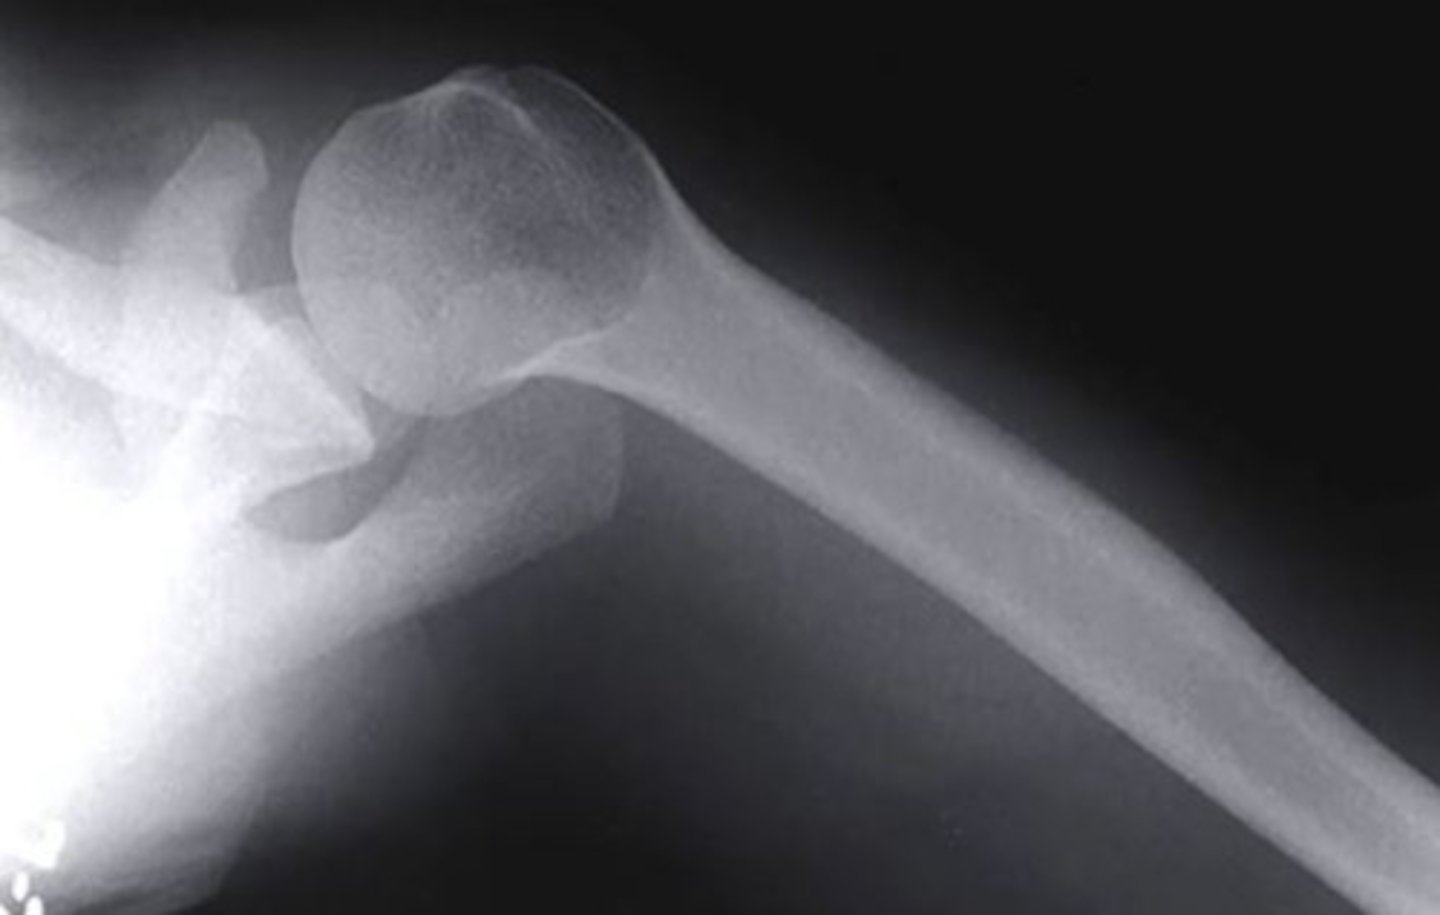

what is the name of this view of the shoulder?

axillary

which structure of the shoulder is highlighted by the blue line in the image?

clavicle